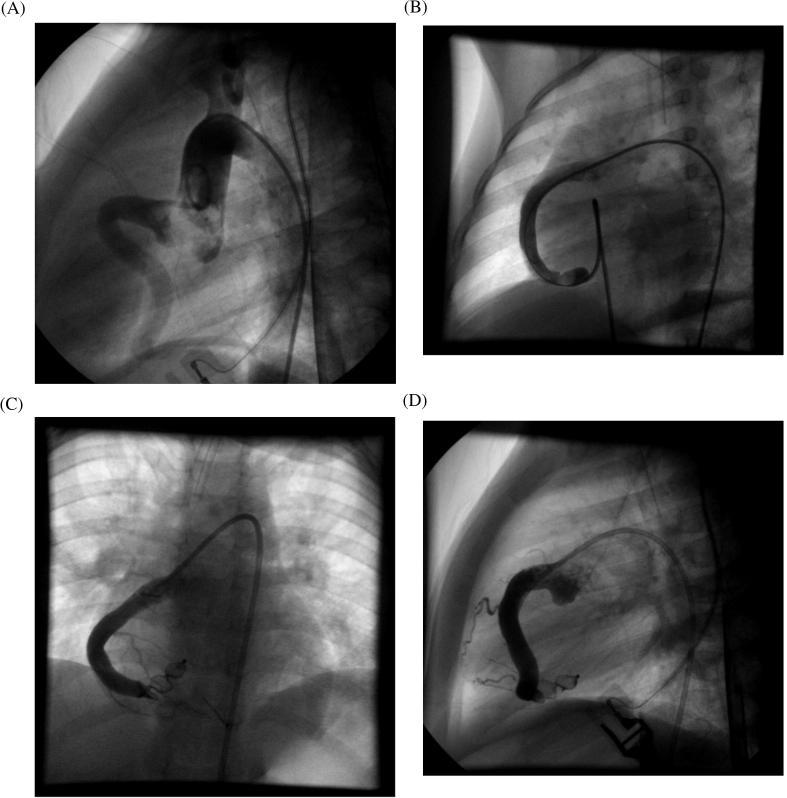

Transcatheter closure of right coronary artery fistula to the right ventricle.

Coronary artery fistula (CAF) is an uncommon anomaly that is usually congenital but can be acquired. Although most patients are asymptomatic, some may present with congestive heart failure, infective endocarditis, myocardial ischemia or rupture. In the past, surgical ligation was the only option in the management of CAF, but since 1983, transcatheter closure of CAF has been increasing as an alternative to surgery. We report a 3-year-old boy, presented in Queen Alia Heart Institute, who underwent successful transcatheter closure of a large fistula communicating the distal part of the right coronary artery to the right ventricle. Our case differs from other CAFs in that the fistula was communicating the right coronary artery itself to the right ventricle.